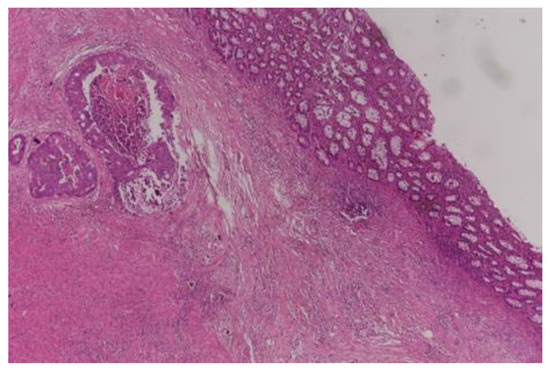

- Dworak, O.; Keilholz, L.; Hoffmann, A. Pathological features of rectal cancer after preoperative radiochemotherapy. Int. J. Color. Dis. 1997, 12, 19–23. [Google Scholar] [CrossRef] [PubMed]

- Ryan, R.; Gibbons, D.; Hyland, J.M.; Treanor, D.; White, A.; Mulcahy, H.E.; O’Donoghue, D.P.; Moriarty, M.; Fennelly, D.; Sheahan, K. Pathological response following long-course neoadjuvant chemoradiotherapy for locally advanced rectal cancer. Histopathology 2005, 47, 141–146. [Google Scholar] [CrossRef]

- Chen, H.Y.; Feng, L.L.; Li, M.; Ju, H.Q.; Ding, Y.; Lan, M.; Song, S.M.; Han, W.D.; Yu, L.; Wei, M.B.; et al. College of American Pathologists Tumor Regression Grading System for Long-Term Outcome in Patients with Locally Advanced Rectal Cancer. Oncologist 2021, 26, e780–e793. [Google Scholar] [CrossRef] [PubMed]